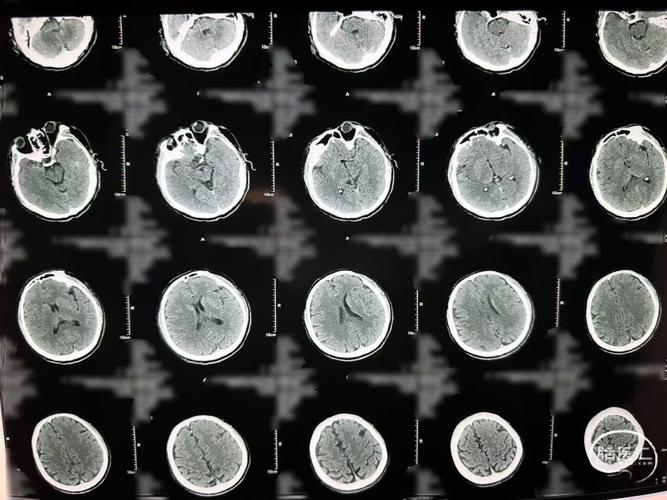

脑梗塞在CT影像上的表现,取决于梗塞灶的病理变化过程,这个过程需要时间。

在这个阶段,脑组织因为缺血缺氧已经开始出现问题,但细胞结构还没有发生足以被CT分辨的密度改变,CT上可能看不到任何异常,或者只能看到一些非常不特异的微小变化,容易被忽略。

早期(发病6-24小时内):CT开始出现细微变化

梗塞灶的中心区域开始发生“细胞毒性水肿”,细胞体积增大,导致局部脑组织密度出现轻微变化,但这个变化非常细微,经验不足的放射科医生也可能难以识别,一些先进的CT技术(如CT灌注成像)可以帮助发现早期缺血,但这不是常规的平扫CT。

确诊期(发病24-48小时后):CT显示清晰梗塞灶

- 病理变化: 梗塞区域的脑细胞开始死亡、崩解,细胞结构被破坏,水分含量显著增加,形成“血管源性水肿”。

- CT影像表现: 在CT图像上,这个区域会呈现出低密度的暗影,因为正常的脑组织密度与脑脊液接近,而梗塞后的组织密度会进一步降低,像一块“被泡发了的脑组织”,与周围正常脑组织形成鲜明对比,诊断脑梗塞就非常明确了。

慢性期(发病数周至数月):CT表现更典型

- 影像变化: 梗塞灶的脑组织会发生液化、坏死,最终形成一个脑软化灶,在CT上,这会是一个边界清晰、永久性的低密度区,其内部甚至可能因为脑组织萎缩而出现与脑脊液密度完全相同的囊腔。